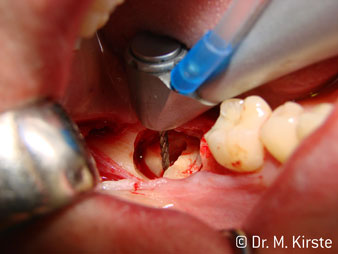

Hızlı çalışmadan bahsetmişken: angldruva, 100,000 rpm üzerinde çalışırken aynı anda profesyonel bir soğutma sağlanır

Angldruva kafası içindeki profesyonel tasarımlı dişliler frezin sessiz çalışmasını garanti eder; kök separasyonu yapılırken atravmatik operasyona olanak verir. (res. 4-9).